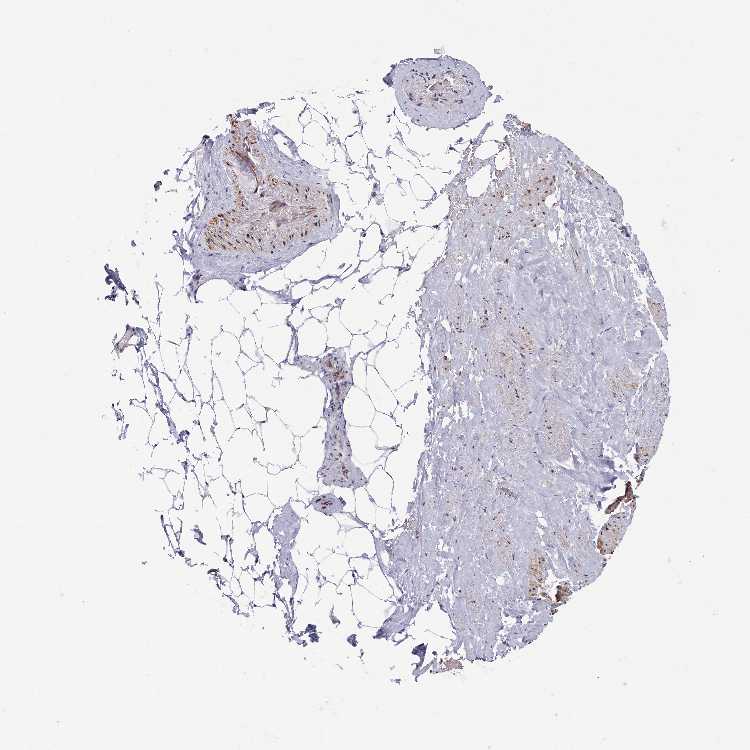

SOFT TISSUE 1 - Antibody stainingi

Antibody staining in the annotated cell types in the current human tissue is reported as not detected, low, medium, or high, based on conventional immunohistochemistry profiling in selected tissues. This score is based on the combination of the staining intensity and fraction of stained cells.

Each image is clickable and will lead to virtual microscopy that enables deeper exploration of all samples and also displays staining intensity scores, fraction scores and subcellular localization as well as patient and tissue information for each sample.

Antibody HPA041766Antibody HPA048639

Chondrocytes -Medium

Fibroblasts LowNot detected

Peripheral nerve LowLow